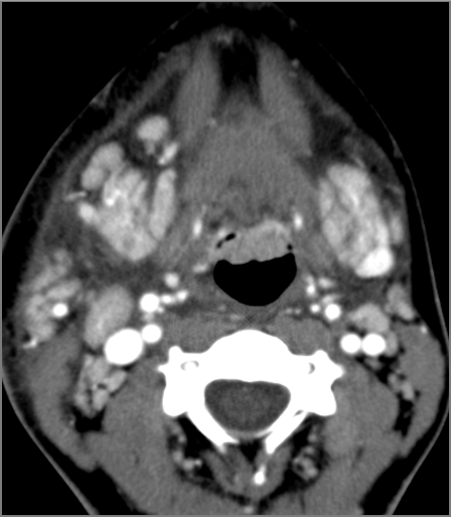

Cervical Lymph Nodes

If there is suppurative cervical adenopathy the purulent material outside the lymph node(s) capsule(s).